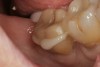

A 70-year-old patient presented with symptoms of a cracked tooth scenario, with intermittent pain upon chewing and thermal sensitivity. The diagnosis was supported through various tests, which determined the lower right second molar had an incomplete fracture that extended from the distal marginal ridge to the mesial marginal ridge. After treatment options were presented, an all-ceramic restoration was decided upon. The tooth was prepared for a nonretentive, adhesively retained all-ceramic restoration ("table top" preparation) (Figure 2 and Figure 3). After the preparation was completed a mild self-etching adhesive was applied to the dentin according to the manufacturer's instruction (Figure 4). There was little concern, if any, of the adhesive reaching the band of exposed enamel. The adhesive was light-polymerized for 5 seconds to secure the layer to the dentin (Figure 5). To eliminate the oxygen-inhibited layer a water-soluble gel was applied to the adhesive and further light-polymerization was completed (Figure 6 and Figure 7). For direct digital scanning cases in which a powdering technique is employed for image capture, it may be more difficult to remove the powder after scanning if the oxygen-inhibited layer is still present.

Figure 2  Facial view (Fig 2) and occlusal view (Fig 3) of nonretentive adhesively retained ("table-top") preparation.

Figure 2

Figure 3  Facial view (Fig 2) and occlusal view (Fig 3) of nonretentive adhesively retained ("table-top") preparation.

Figure 3